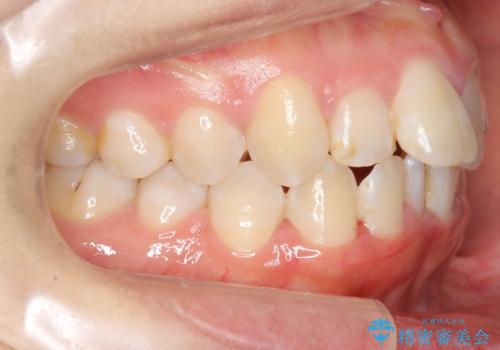

上下の前歯のがたつき 歯を抜かずに矯正

- 上下の前歯のがたつきを主訴に来院。

歯を抜かずに前歯を揃えています。

奥歯を後ろに下げたりなどはしていません。

奥歯を外に広げ、前歯中心に歯を少し削っていますが、健康には問題ない範囲で行なっています。